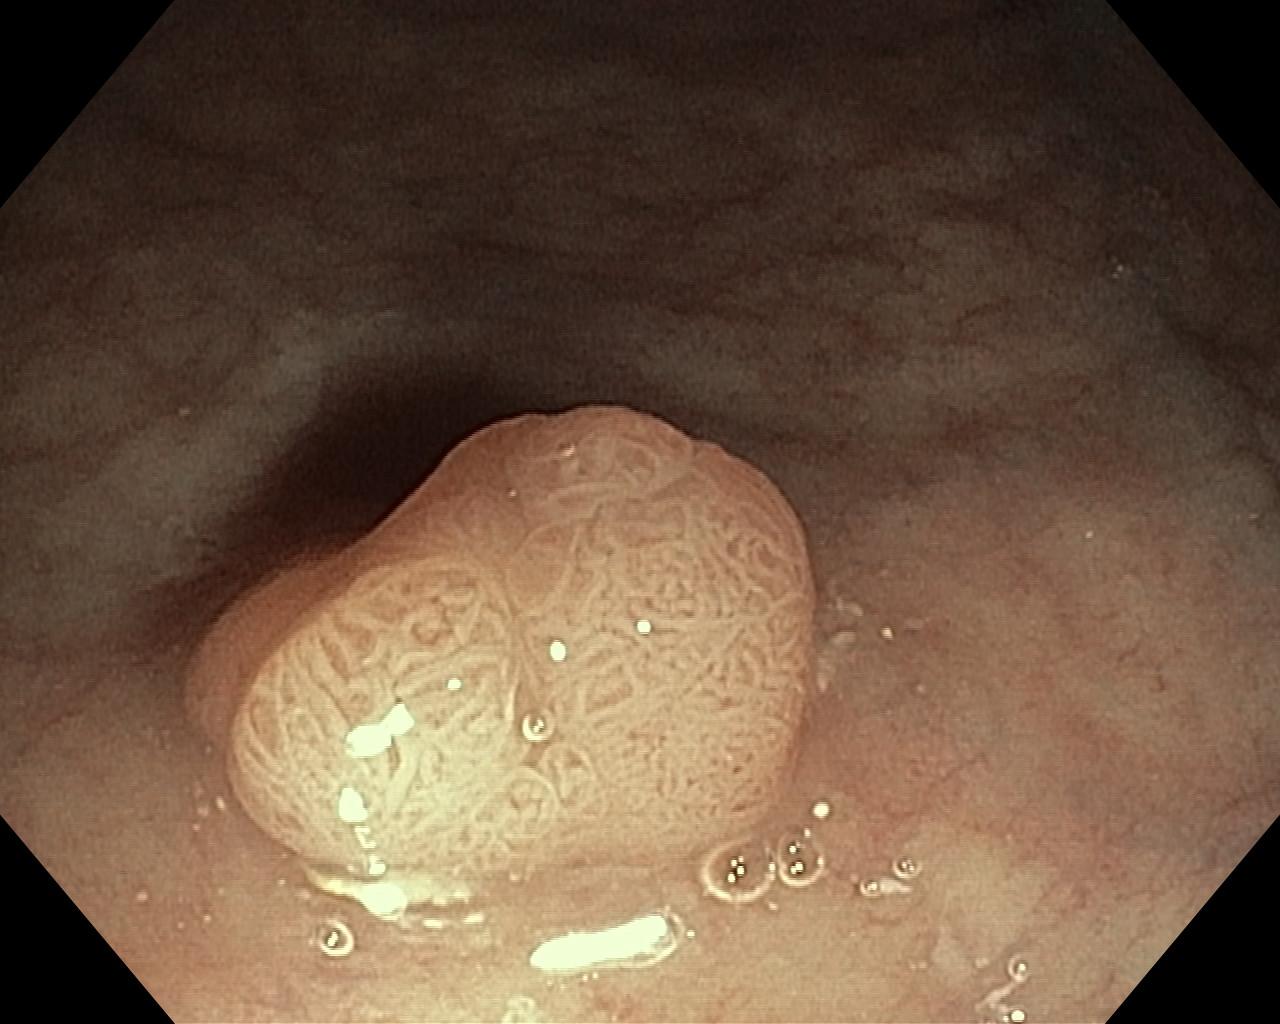

Polipy